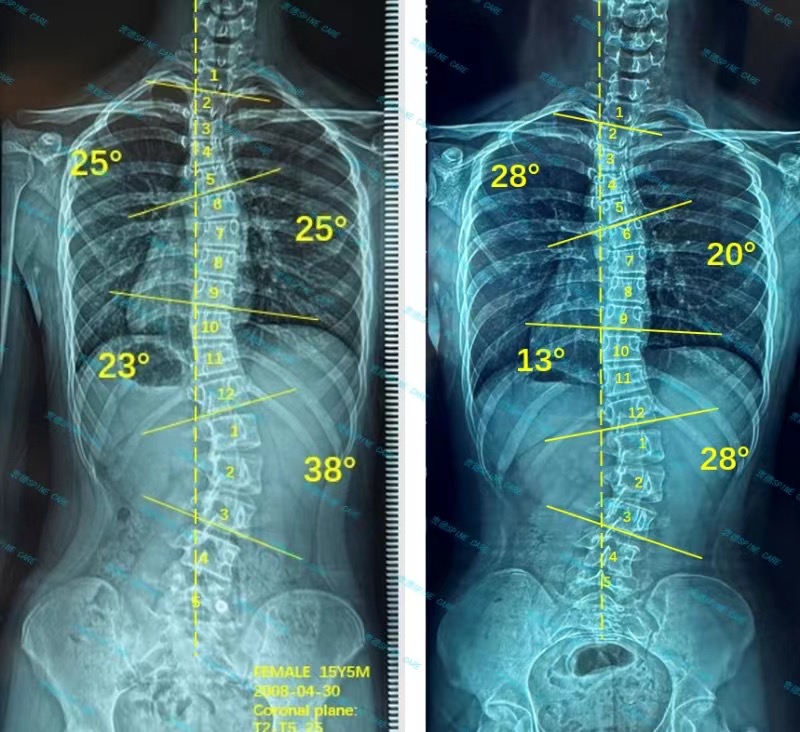

案例主人:诺诺 发现侧弯年龄:15岁 侧弯情况:Cobb角度38度

在衷德治疗一年后我的度数已经回来了10度,从38度降低至28度,骨盆也正了不少,一直到现在我还在衷德脊柱坚持训练。

After one year of treatment in Zhongde, my degree has returned to 10 degrees, from 38 degrees to 28 degrees, and my pelvis has also been corrected a lot. I still continue to train in Zhongde Spine until now.